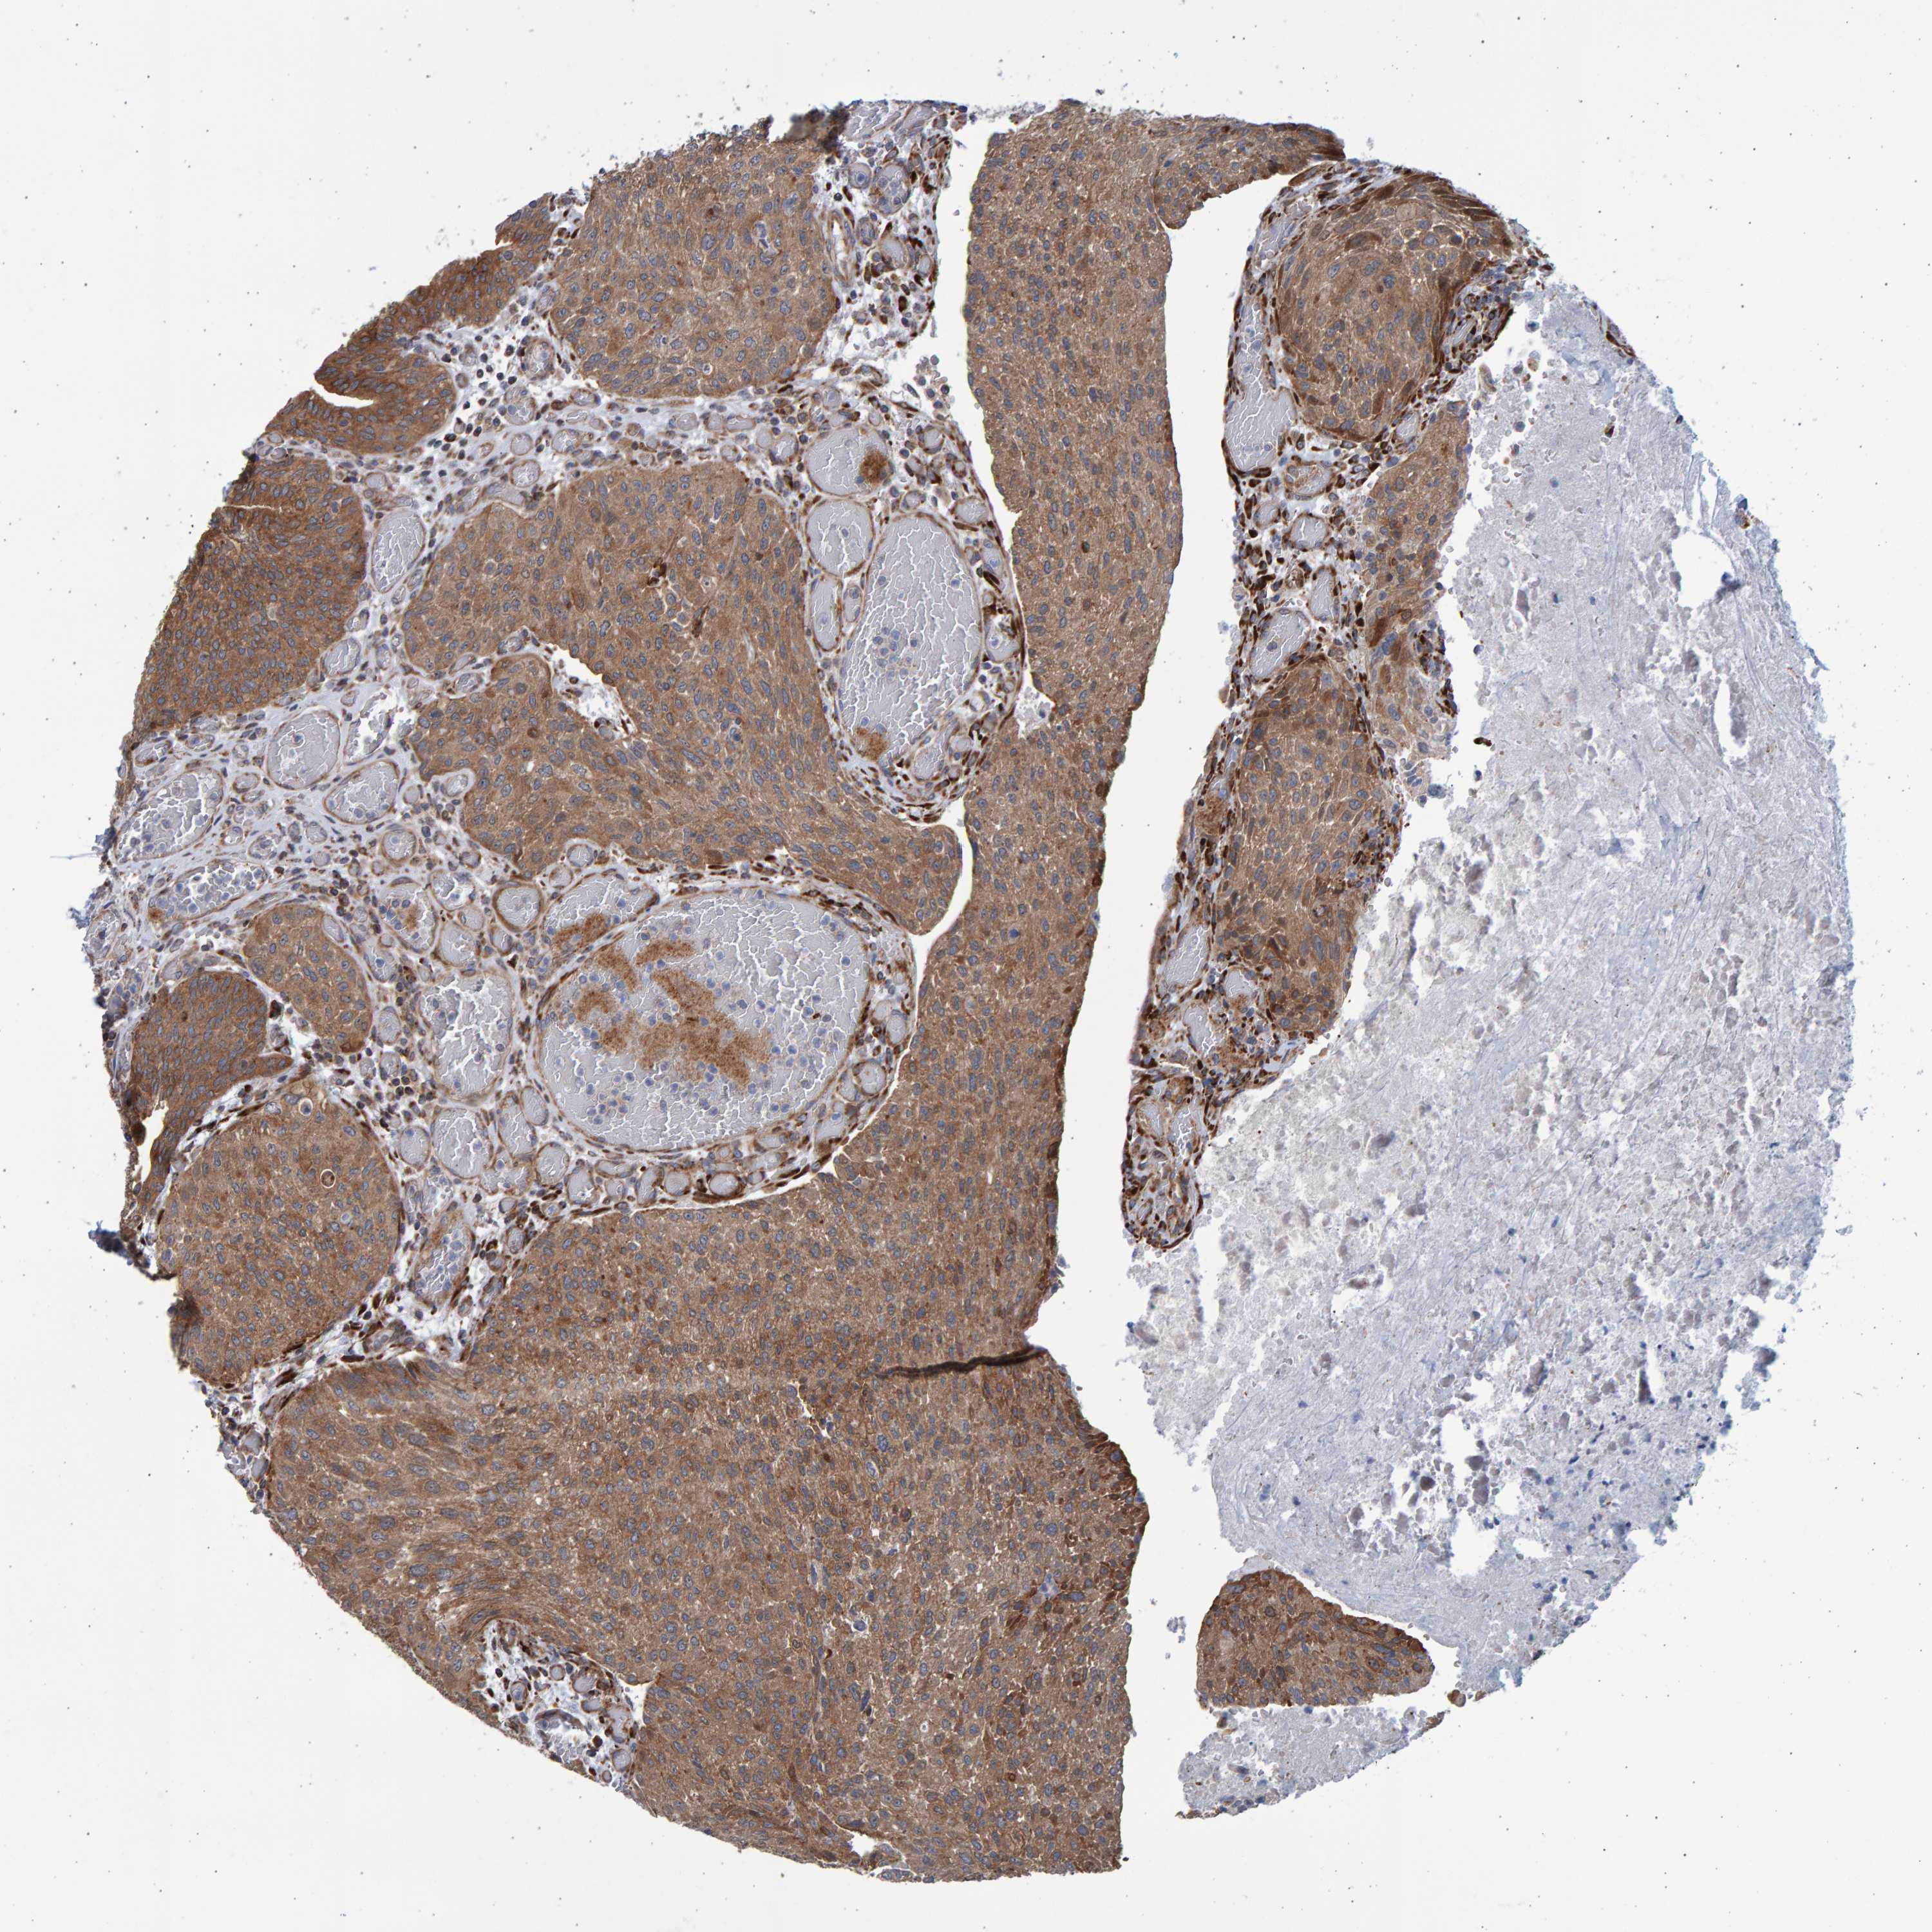

UROTHELIAL CANCER - Protein expressioni

A mouse-over function shows sample information and annotation data. Click on an image to view it in a full screen mode. Samples can be filtered based on level of antibody staining by selecting one or several of the following categories: high, medium, low and not detected. The assay and annotation is described here.

Antibody stainingi

Antibody staining in the annotated cell types in the current human tissue is reported as not detected, low, medium, or high, based on conventional immunohistochemistry profiling in selected tissues. This score is based on the combination of the staining intensity and fraction of stained cells.

Each image is clickable and will lead to virtual microscopy that enables deeper exploration of all samples and also displays staining intensity scores, fraction scores and subcellular localization as well as patient and tissue information for each sample.

Antibody HPA023597

Urothelial carcinoma, Low grade

Urothelial carcinoma, High grade